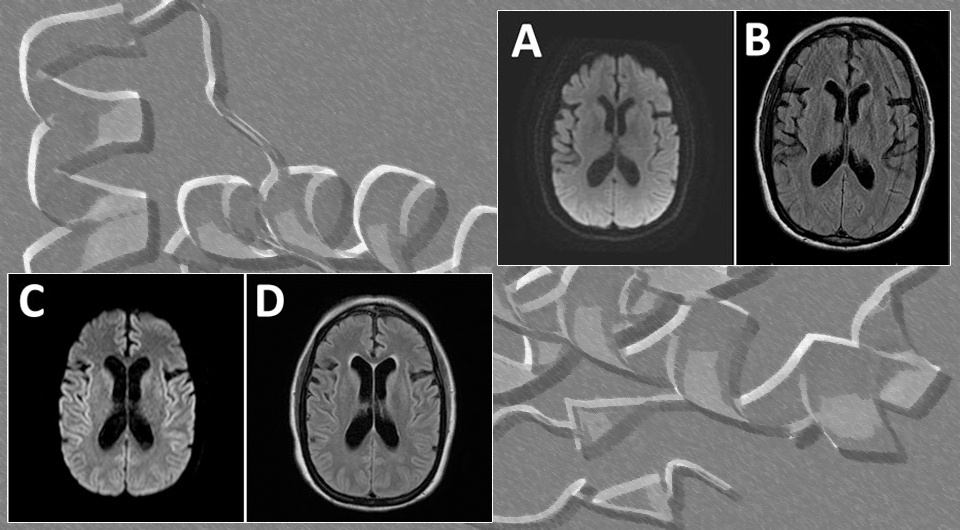

Несмотря на лечение, улучшения не было. Повторная МРТ выявила дегенеративные изменения в мозге, а специфические анализы показали аномально высокий уровень белков, характерных для прионных заболеваний. Был проведён тест RT-QuIC — он подтвердил присутствие прионов.